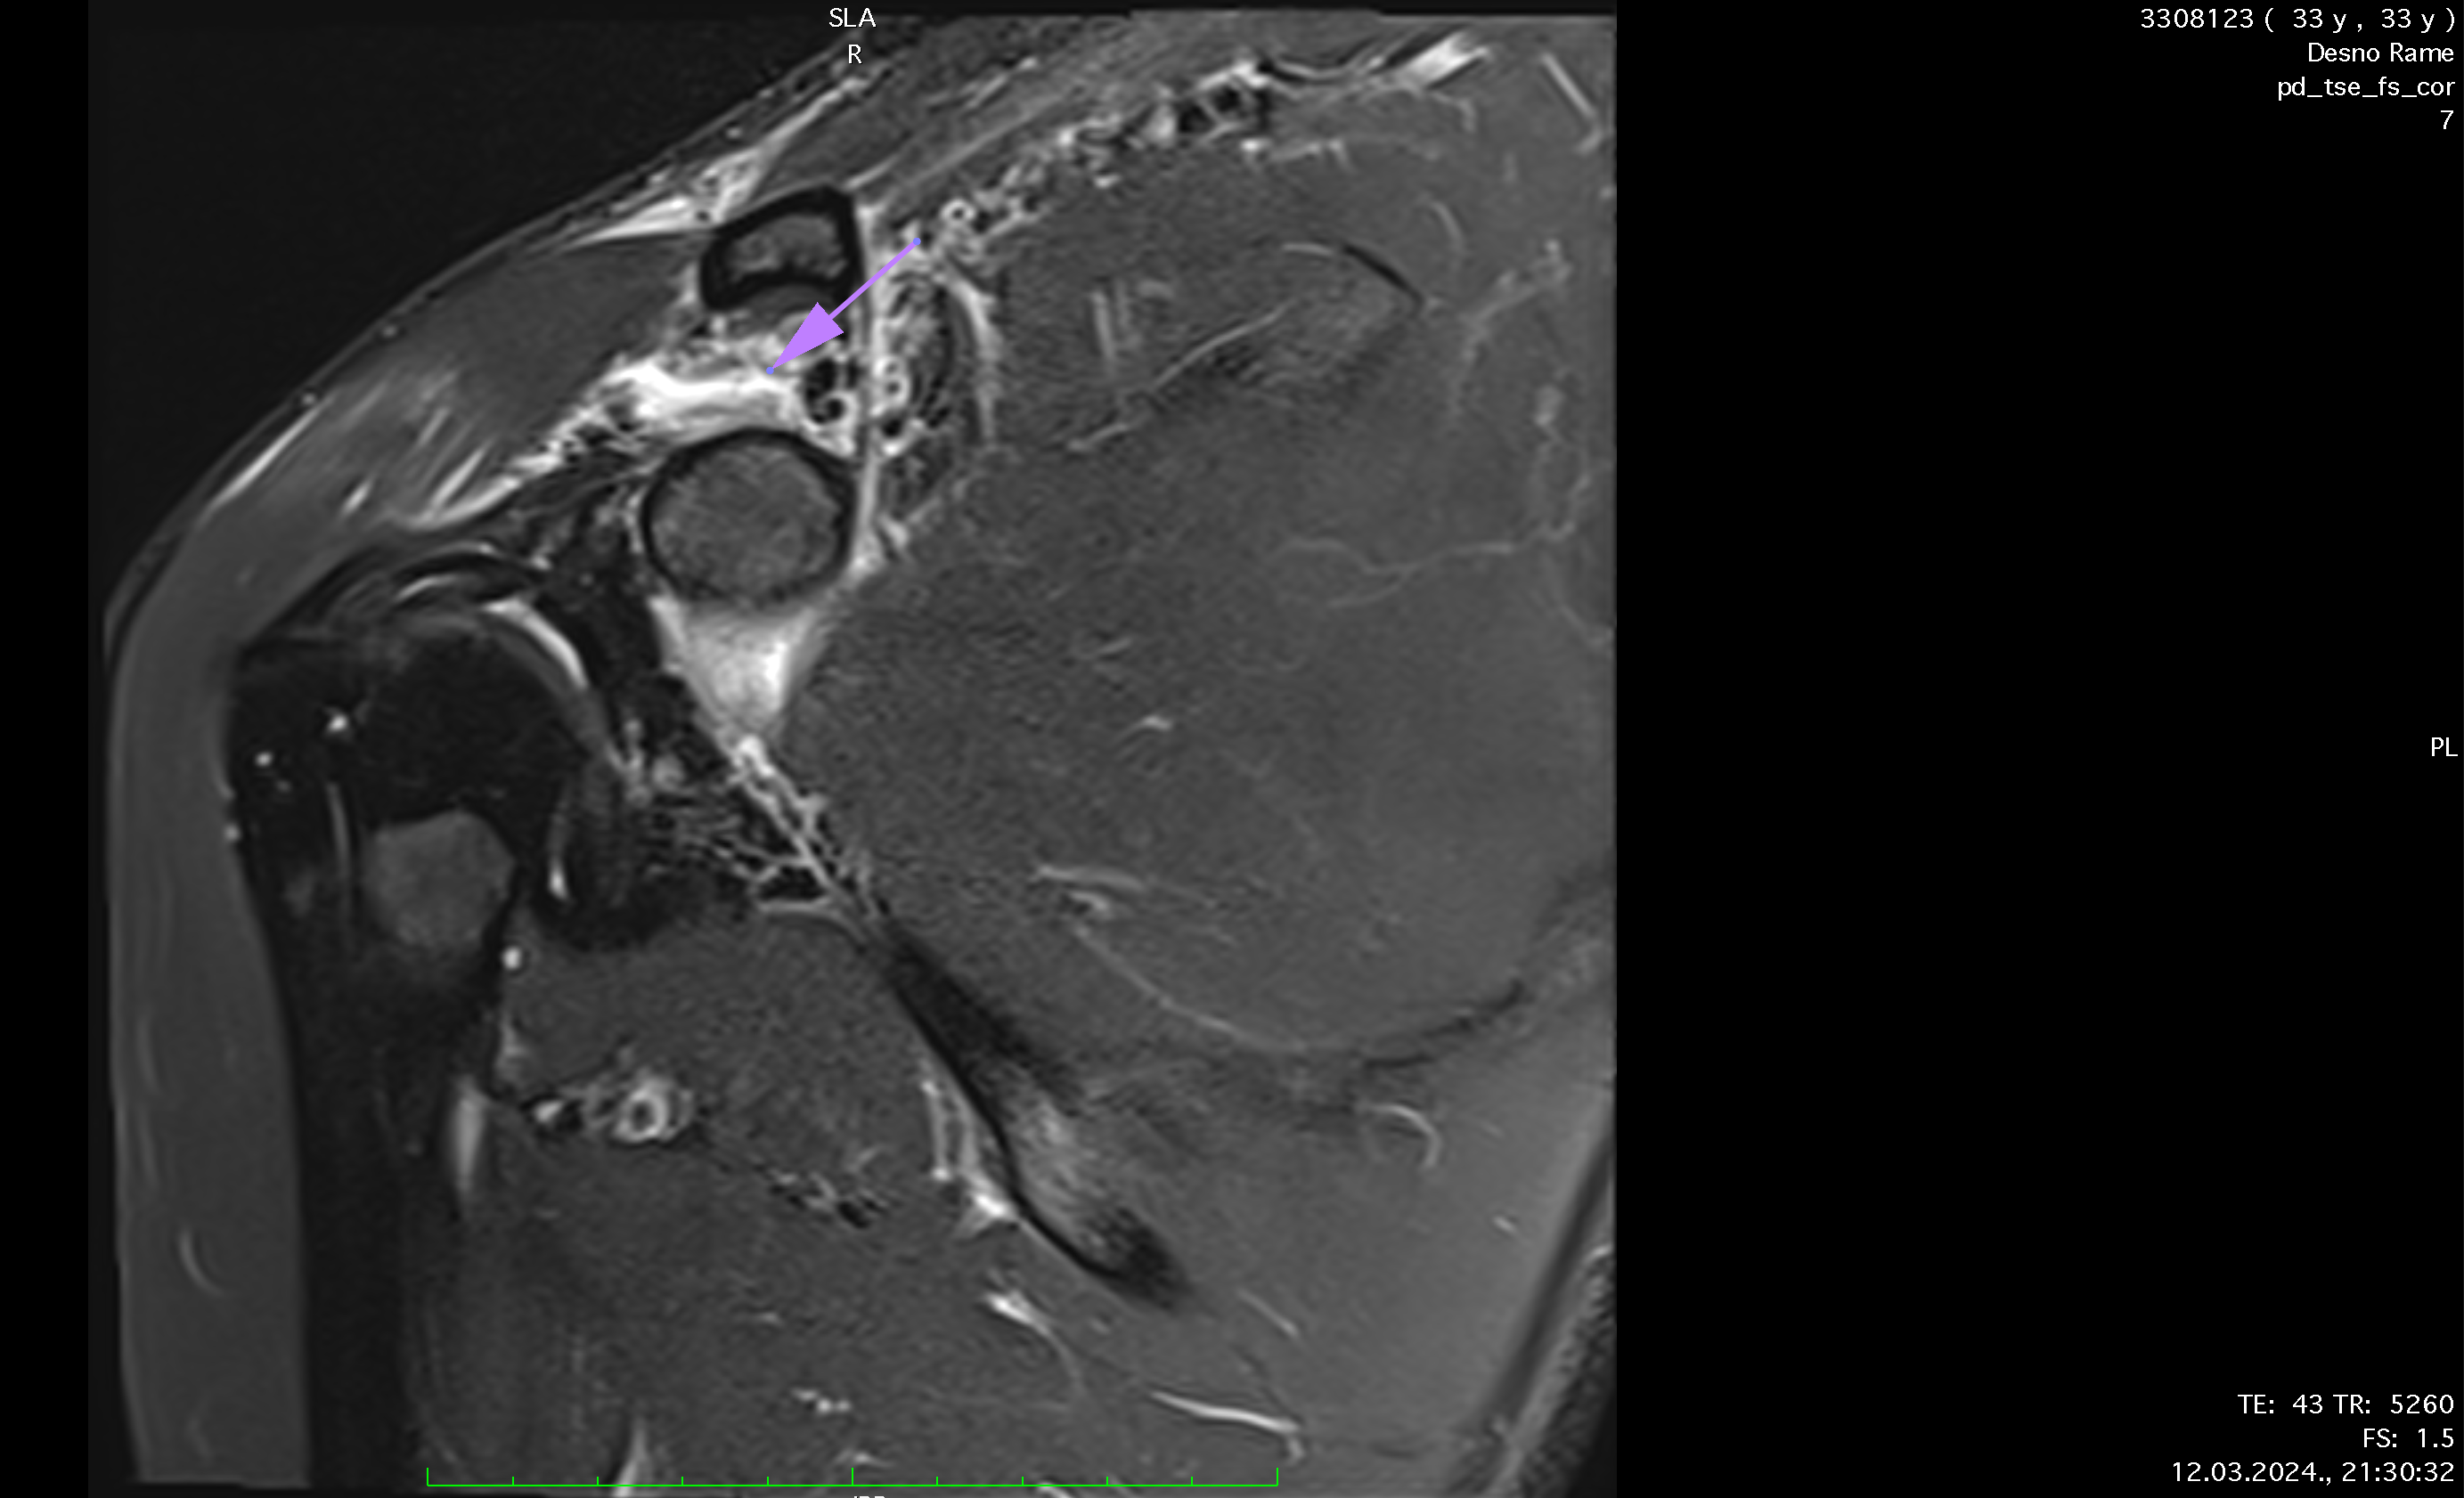

Ten days after the injury, the player's pain level had decreased to 3 out of 10, and nearly full ROM had been regained. A follow-up MRI showed significant recovery, with the AC joint fully reconnected and healed ligaments, though there was some residual edema caused by inflammation from the prolotherapy. Treatment continued for another week, during which the player engaged in more active exercises, including mobility, weight-bearing, and rotator cuff strengthening. While fast movements initially caused stiffness, this resolved within 3 to 4 days.

Reconnection of coracoclavicular ligament, soft tissue, trapezius m., regeneration, formation of AC joint capsule visible after only 8 days of therapy.